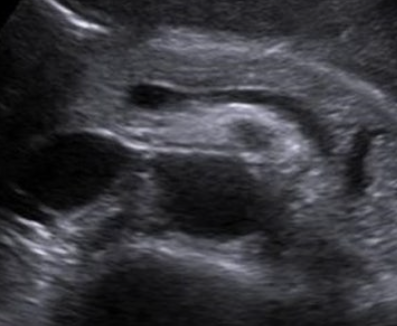

침묵의 장기, 췌장이 보내는 위험 신호: 초기 췌장염, 놓치지 마세요

췌장은 우리 몸에서 소화 효소와 호르몬(인슐린)을 생산하는 중요한 장기입니다. 췌장염은 이러한 췌장에 염증이 생기는 질환으로, 초기에는 증상이 미미하여 간과하기 쉽습니다. 하지만 방치하면 심각한 합병증을 초래할 수 있으므로, 초기 증상을 인지하고 적절한 대처를 하는 것이 중요합니다.

- 즉시 병원 방문: 소화기내과 전문의에게 진료를 받고 정확한 진단을 받아야 합니다. 혈액 검사, 복부 CT, MRI 등의 검사를 통해 췌장염 여부와 원인을 확인할 수 있습니다.